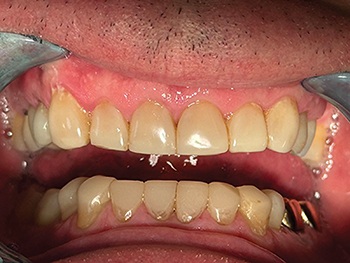

Shaw emphasized the importance of proper isolation for predictable bonding. Using a 90N clamp and rubber dam (Fig. 2), he sandblasted the tooth surfaces before etching to ensure bonding to a clean substrate. Much of the lower incisor work required bonding directly to dentin, making technique and moisture control essential to long-term success.

Fig. 2: Rubber dam isolation